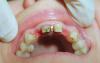

Andex Опубликовано 3 декабря, 2012 Поделиться Опубликовано 3 декабря, 2012 Коллеги, хочу поделиться с вами опытом своей работы. Импланты 3,3 х 10 в позиции 12 и 22. Надеюсь на конструктивную критику и пожелания приветствуются. Извиняюсь за качество фото.Ситуация до начала (между резцами остатки временного цемента)Установлены имплантыУшилсяВид с временной реставрацией на ближайшие 6 месяцевРентген сразу после установки Ссылка на комментарий

Andex Опубликовано 3 декабря, 2012 Автор Поделиться Опубликовано 3 декабря, 2012 pawa прав, доктор пока не умеет, почему и просит советов на будующее, чтобы знать что требуется сделать. Позиционирование - старался как на лекциях объясняли, протезировать сам собираюсь, хотел максимально подготовить условия для качественной протетики. торк 40 нъютонов, с момента удаления корней 12 и 22 до иплантации прошел год (пациентка потерялась, сказала устраивали временные коронки, а пришла только когда они расцементировались), тут объяснили необходимость продолжения лечения) Ссылка на комментарий

Andex Опубликовано 4 декабря, 2012 Автор Поделиться Опубликовано 4 декабря, 2012 какие именно импланты поставили?? SPI?? 12 - SPI, 22 - DFI Ссылка на комментарий